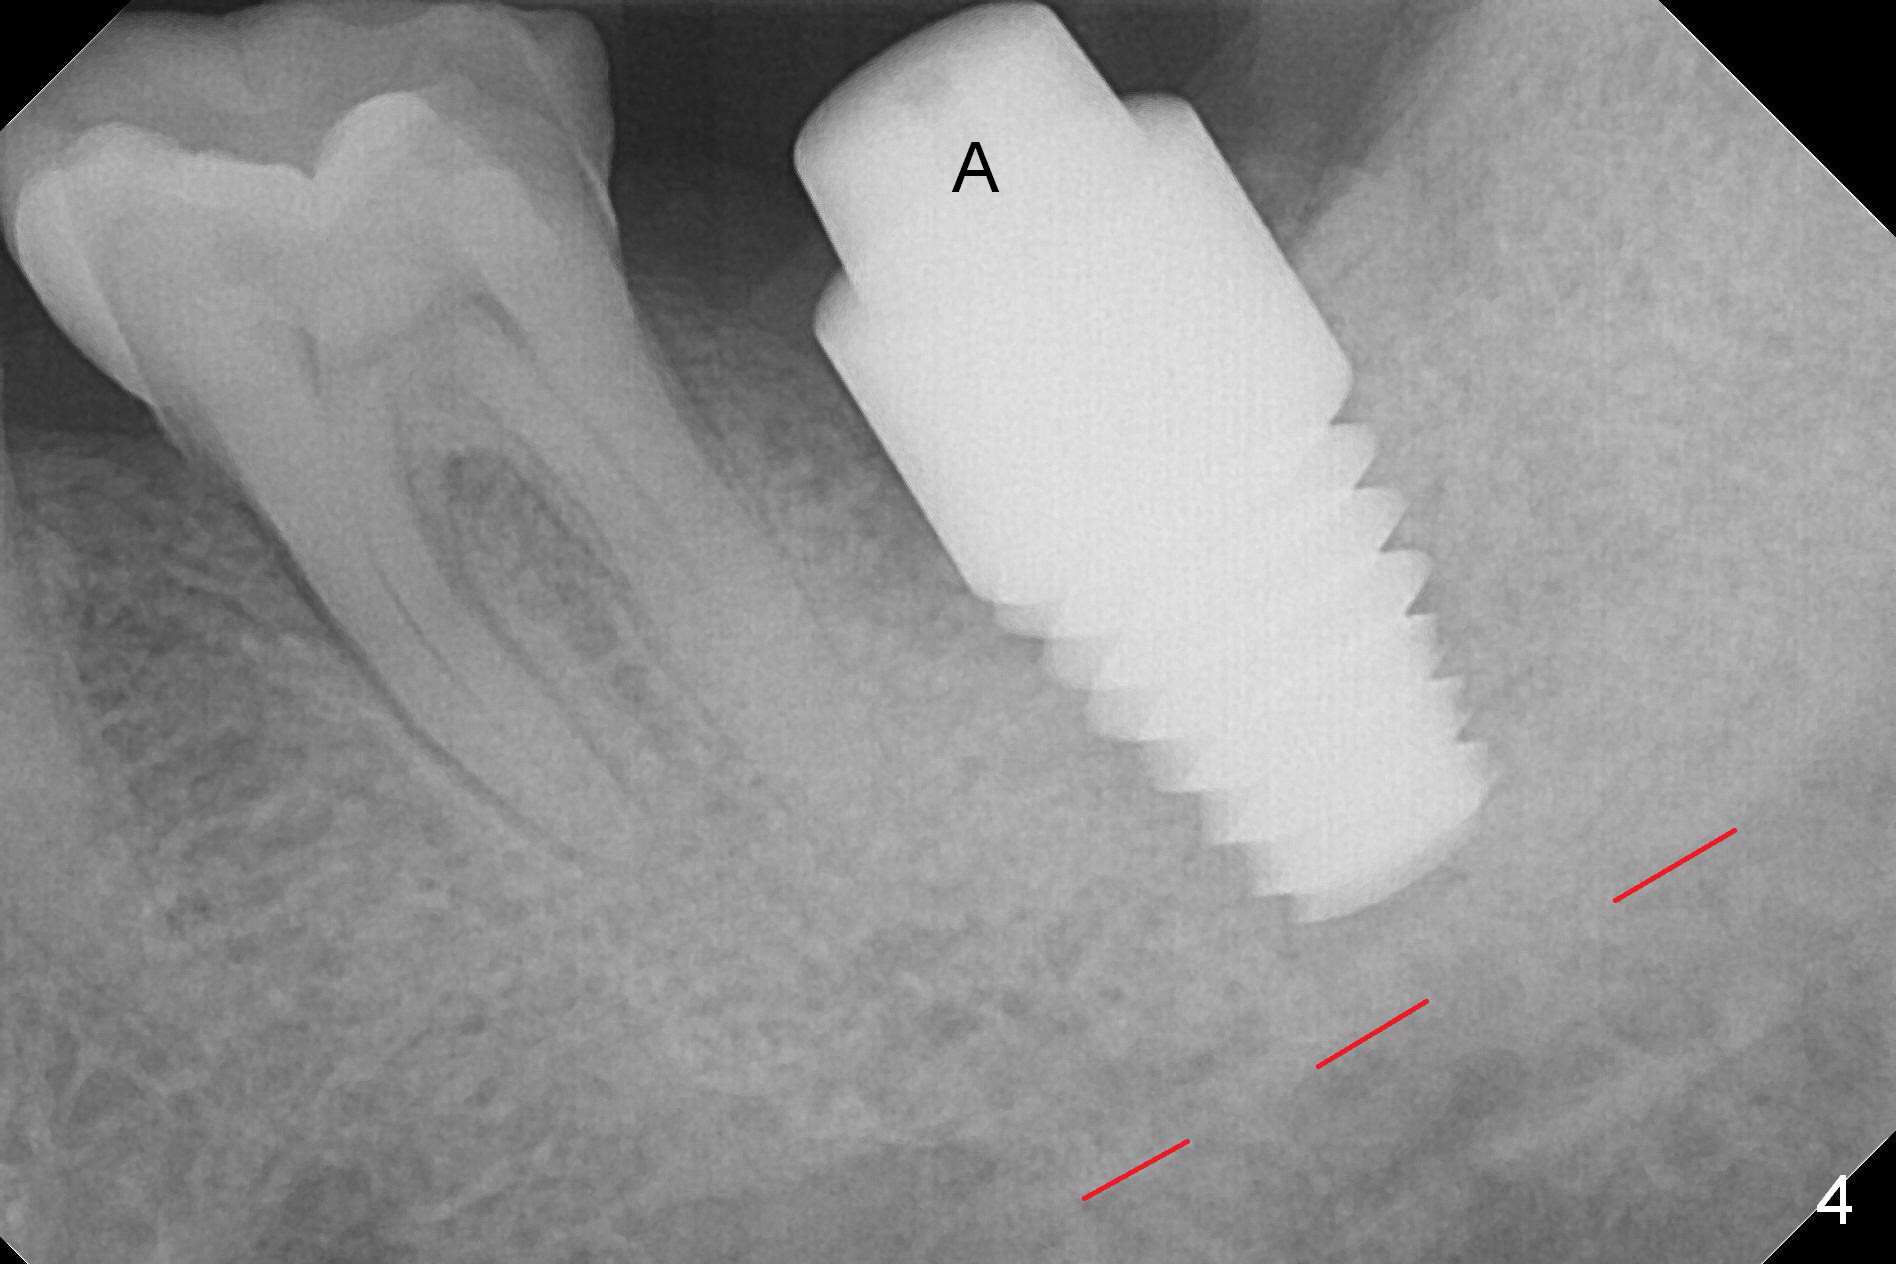

When the tooth #18 is extracted, the buccal and lingual plate are absent. Initial osteotomy is established in the middle of the socket (Fig.1). After 4.3 mm Magic Drill (15 mm from the buccal gingival margin, new bone ~ 4 mm), a 5x9 mm IBS dummy implant is placed with correct trajectory (Fig.2). Since the bone density is seemingly high, the same size of a definitive implant is placed with primary stability. The trajectory is found not ideal after bone graft and insertion of an abutment (data not shown). The stability is lost when the trajectory is changed. No primary stability is achieved with a larger (5.5x9 mm) implant. Tatum tapered taps (6x17, 7x17 and 8x17 mm) are used. The latter obtains stability with contact with the mesial and distal crests (Fig.3 *). A 8x14 mm tissue-level implant is placed with insertion torque ~ 55 Ncm (Fig.4). A 6x3 mm abutment (Fig.4 A) is placed to retain an immediate provisional (Fig.5 P). The drawback of the extra large implant is lack of bone buccolingually. Oral hygiene is emphasized so that the buccal and lingual bone have chance to regenerate. Fortunately there appears to be no paresthesia postop.

It appears that the patient chews on the left postop, since the provisional perforates with loose abutment nearly 3 months postop and the tooth #3 has occlusal sensitive chip. The implants seems to have osteointegrated (Fig.6). To improve oral hygiene, the provisional is not recemented. The patient will return for impression in 2 weeks. It appears that there is short healing time for large implant. There is no bone loss 7 months post cementation (Fig.7). The buccal gingiva is lightly erythematous without tenderness 1 year 7.5 months post cementaion. Water pik is being used, although chronic periodontitis is not under control. Retrospectively, surgery should be shifted to socket preservation when a moderate implant (5 or 5.5 mm) fails to achieve primary stability. The extra large implant (8 mm for example) leaves a little gap buccolingually. Guided surgery would allow precise placement of the moderate implant without change in trajectory. The crown becomes loose because of occlusal perforation and limited vertical space. When a new crown is cemented, the bone density around the coronal threads is high (Fig.8 *). While the bone remains stable at #4 (6 months post RCT), 13 (4 years 6 months post cementation) and 18 (2 years 5 months post cementation), there is severe bone loss at #2 and 31 (Fig.9).